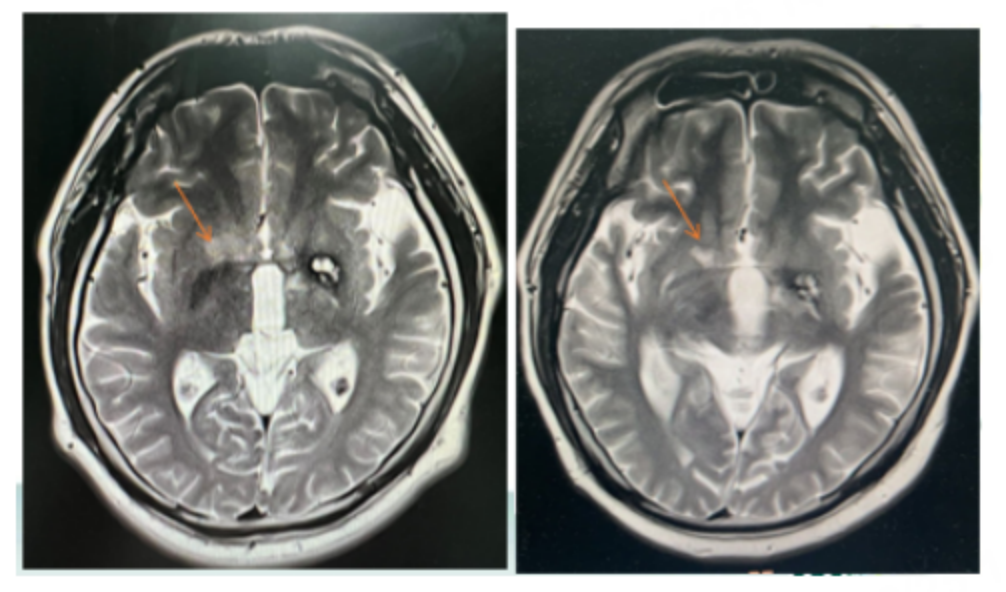

影像结果:2年前因右侧肢体无力就诊,影像提示颅内左基底节区占位(图1)。

图1:影像结果

病理免疫组化结果:立体定向穿刺活检提示AE1/AE3(-)、CD3(-)、CD20(+)、CD30(-)、Ki-67(阳性细胞数70%)、CD21(-)、Bc1-2(-)、Bc1-6(+)、CD10(-)、CD5(-)、CD23(-)、CyclinD1(-)、CD38(-)、C-myc(30%阳性)、MUM1(+)、Pax-5(+)。原位杂交结果提示EBER(-),高级别B细胞淋巴瘤,考虑为PCNS-DLBCL。

放化疗后复发:化疗结束后6个月首次复发,头颅MR提示新发右侧基底节区信号异常。放疗(全脑放疗36Gy及局部病灶放疗46Gy)结束10个月后二次复发,出现头晕,头颅MR提示新增双侧基底节区异常强化信号。